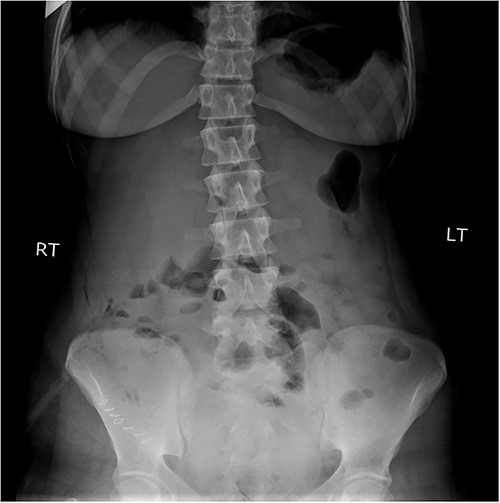

An 18-year-old female patient, with free past medical and surgical history, presented to the emergency department because of abdominal pain of 5-day duration associated with nausea, vomiting, constipation and loss of appetite. The pain was all over the abdomen mostly in the right lower quadrant, of gradual onset, colicky in nature, not radiated with any aggravating or relieving factors. It started intermittently and became continuous with increasing severity on the day of admission. On admission, she had normal vital signs. Physical examination showed a mildly distended abdomen with exaggerated bowel sounds. The patient had abdominal tenderness mostly in the right lower quadrant with abdominal guarding. Rovsing sign and rebound tenderness were both positive. However, the psoas and obturator signs were negative. No scars, hernias or masses were found. Laboratory tests are all within normal. A plain abdominal X-ray demonstrated air-fluid levels of the small bowel, with no pneumoperitoneum (Fig. 1). Abdominal ultrasound showed bowel wall thickening in the ileum, a target-like mass containing a central area of increased echogenicity with a double target appearance. The initial diagnosis was a small bowel obstruction. Because of the severity of the abdominal pain, a decision to proceed with diagnostic laparotomy was made. Nasogastric decompression was done, IV fluids, antispasmodics and antibiotics were started. The patient underwent emergency surgery with a lower midline abdominal incision. Intraoperatively, an intussuscepted segment of the ileum measuring 8 cm in length located 75 cm from the ileocecal valve with dilated proximal ileal and jejunal loops was found and a soft polypoid shape mass was palpable within the lumen (Fig. 2). Enterotomy was performed revealing a tubular segment measuring 6 × 2 × 0.8 cm with a globular swelling at the tip (Fig. 3). No ischemic loop was identified. A diverticulectomy was performed in parallel with the longitudinal axon of the bowel lumen. Ectopic gastric mucosa was identified histologically confirming the diagnosis of inverted MD. The postoperative period was uneventful. CT scan with oral and IV contrast postoperative Day 5 showed no leak from the site of anastomosis (Fig. 4). The patient started a soft diet on Day 5 and was discharged on Day 7.

Plain abdominal X-ray demonstrated air-fluid levels of the small bowel.